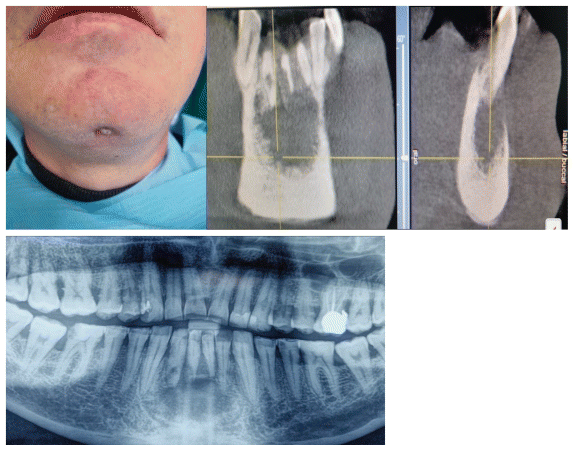

A 46-year-old male presented with aesthetic deformity in the mentum region. Clinical examination revealed firm, non-tender mental swelling with an associated cutaneous fistula. CBCT imaging demonstrated a well-circumscribed radiolucent periapical lesion (2.5 × 1.8 cm) associated with mandibular anterior teeth, consistent with a suppurated radicular cyst (Figure 1–2).